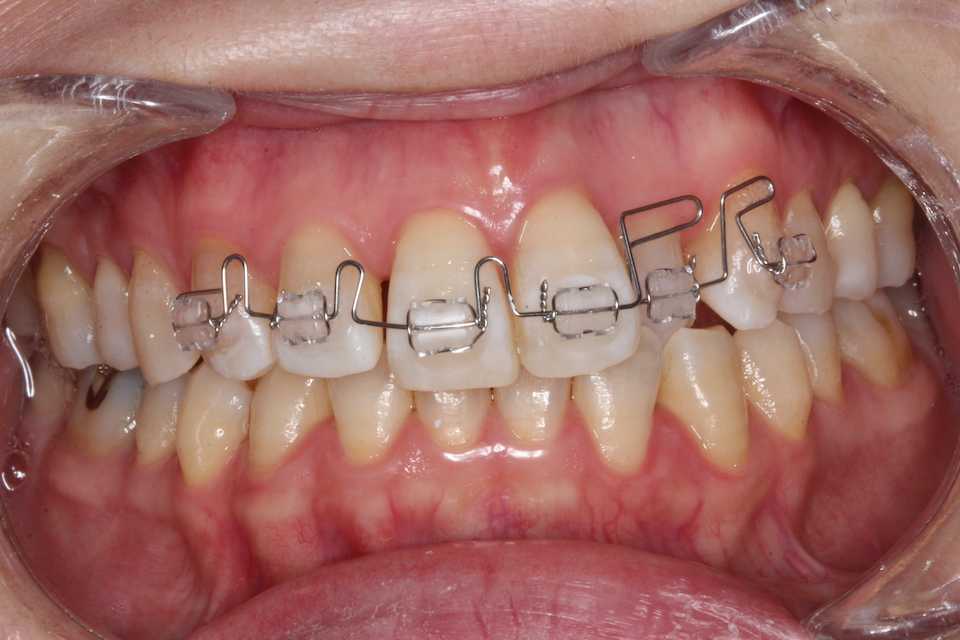

拡大症装置を2年程使って十分広がって、動かすスペースができたのでブラケット&ワイヤーを装着した。

最初はレベリングと言ってブラケットのスロット(ワイヤーの入る溝)を一列にする工程。

ワイヤーは丸014"